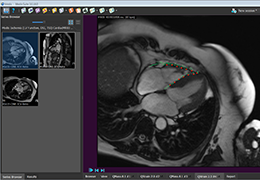

ANYTHINK 经导管主动脉瓣膜置换术分析系统